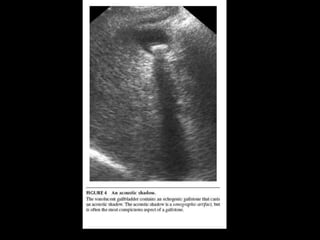

TYPICAL SONOGRAPHIC

APPEARANCE OF

GALLSTONE

UNDER WHAT CIRCUMSTANCES

WOULD THE GALLBLADDER NOT

HAVE ITS TYPICAL APPEARANCE?

• When patient has recently eaten.

• Multiple episodes of cholecystitis (scarred and

shrunken)

• Filled w/stones or contracted around

gallstones

• Air filled gallblader (empysematouse

cholecystitis)

TYPICAL SONOGRAPHIC APPEARANCE OF GALLSTONE

UNDER WHAT CIRCUMSTANCES WOULDTHE GALLBLADDER NOT HAVE ITS TYPICAL APPEARANCE?

• When patienthas recently eaten. • Multiple episodes of cholecystitis (scarred and shrunken) • Filled w/stones or contracted around gallstones • Air filled gallblader (empysematouse cholecystitis)